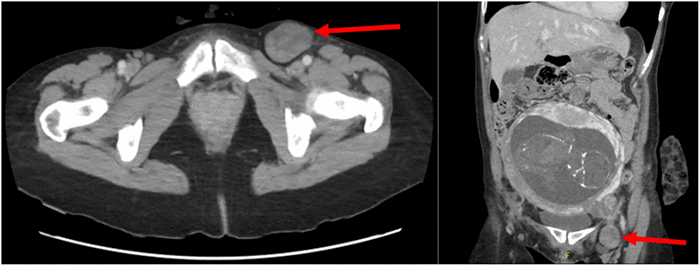

Subsequent CT scan revealed a left groin mass (Figure 1), likely representing a femoral hernia with suggestion of torsion of the fallopian tube and/or the left ovary. Laboratory values were unremarkable, and a beta hCG level was 7381mIU/mL. Medical and surgical history was notable for a prior right tubal pregnancy managed with methotrexate, a reducible umbilical hernia, and recent negative EGD/Bronchoscopy for hemoptysis of unknown origin. Following the history and physical examination as well as review of the lab work and imaging, the patient was urgently taken to the operating room.

Figure 1. Preoperative CT Scan. Published with Permission

A) Axial and B) coronal view of the CT scan showing the femoral hernia (arrows).